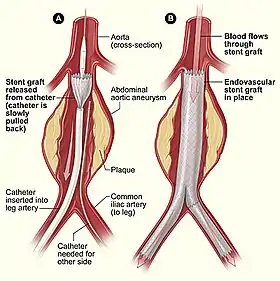

Endovascular aneurysm repair (EVAR) is a type of minimally-invasive endovascular surgery used to treat pathology of the aorta, most commonly an abdominal aortic aneurysm (AAA). When used to treat thoracic aortic disease, the procedure is then specifically termed TEVAR for "thoracic endovascular aortic/aneurysm repair." EVAR involves the placement of an expandable stent graft within the aorta to treat aortic disease without operating directly on the aorta. In 2003, EVAR surpassed open aortic surgery as the most common technique for repair of AAA,[1] and in 2010, EVAR accounted for 78% of all intact AAA repair in the United States.[2]

Technique

The procedure is carried out in a sterile environment under fluoroscopic guidance. It is usually carried out by a vascular surgeon, interventional radiologist or cardiac surgeon, and occasionally, general surgeon or interventional cardiologist.[9][10][11][12] The procedure can be performed under general, regional (spinal or epidural) or even local anesthesia. [13]

Access to the patient's femoral arteries can be with surgical incisions or percutaneously in the groin on both sides. Vascular sheaths are introduced into the patient's femoral arteries, through which guidewires, catheters, and the endograft are passed.

Diagnostic angiography images are captured of the aorta to determine the location of the patient's renal arteries, so the stent-graft can be deployed without blocking these. Failure to achieve this will cause kidney failure. With most devices, the "main body" of the endograft is placed first, followed by the "limbs" which join the main body and extend to the iliac arteries, effectively protecting the aneurysm sac from blood pressure.

The endograft acts as an artificial lumen for blood to flow through, protecting the surrounding aneurysm sac. This reduces the pressure in the aneurysm, which itself will usually thrombose and shrink in size over time.[14]